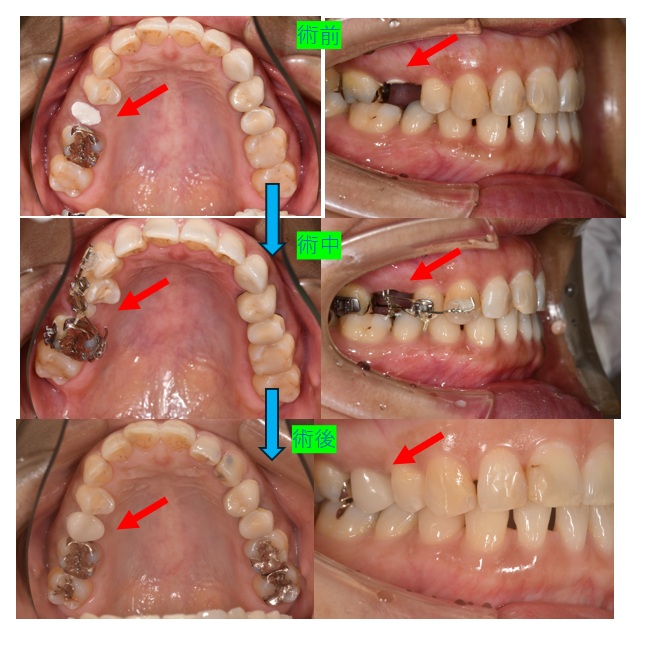

症例ー歯根破折して冠脱離したが、再度、冠作成して保存した

前医で冠をいれてもらった部位が、食事中に脱離してきたと言われました。

痛みなく、冠脱離した部位は、根のみ残っておりました。完全な破折です。

この症例は、歯根の長さも十分にあるので、エクスルージョン方法を用いての保存治療を行いました。

エクスルージョン方法とは、以下のイラストように、根を引き上げて、通常の冠を入れられる状態に改善する方法です。

残っている根を引き上げるのに、ゴムの張力を利用します。

周期的に来院して頂き、ゴムの劣化の為に、ゴムの交換が必要です。

1週間に1回ペースで来院していただき、ゴムの交換を行います。

また、根が引き上げられると、上部のワイヤーに当たり始めます。その時は、再度、根のU字のバーの調整が必要です。

終了の目安は、健全な歯質が周囲の歯肉より、すべて出てきている状態です。

上記のように、新しい冠を入れて保存治療の終了です。